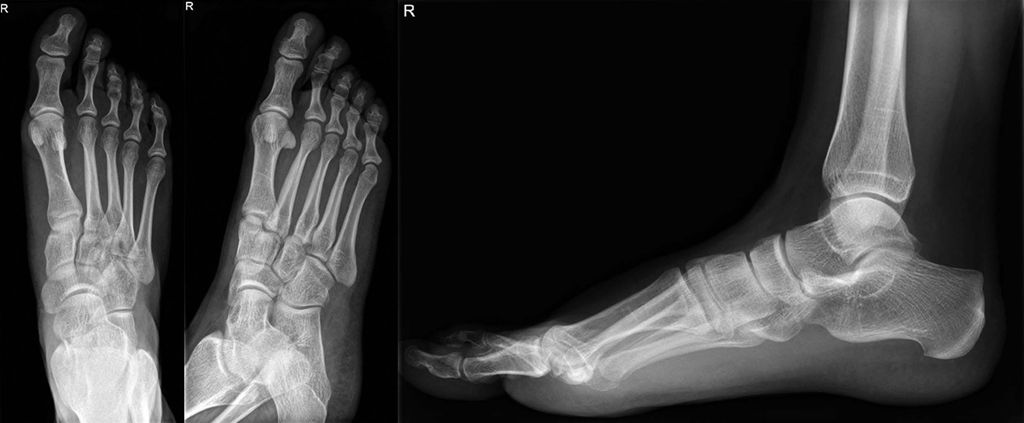

Die definitive Versorgung wird nun mit einer von medial durch das Os cuneiforme mediale schräg in die Basis des Os metatarsale II aufsteigenden Stellschraube zur Fixation des cuneimetatarsalen Gelenkes zwischen dem Os cuneiforme mediale und der Basis des Os metatarsale II begonnen (Abb. 6). Die Tarsometatarsalgelenke I–III werden anschließend mit winkelstabilen Plattensystemen im Sinne eines Fixateur interne überbrückt. Die Kirschnerdrähte werden entfernt, nur an den Tarsometatarsalgelenken IV und V können bei ausreichend stabil erscheinender Fixation der Tarsometatarsalgelenke I–III die Kirschnerdrähte belassen werden, da sich durch die Stabilisierung der Gelenke I–III üblicherweise eine ausreichende Stabilität im Lisfranc-Gelenk der Strahlen IV–V ergeben hat. Erscheint dies nicht ausreichend, etwa durch begleitende Frakturen, sind auch die Strahlen IV und V mit einer winkelstabilen Plattenosteosynthese zu versorgen (Abb. 7).

Anschließend erfolgt der Wundverschluss. Eine zusätzliche Fixation durch einen Fixateur externe ist nicht mehr notwendig (Abb. 8).